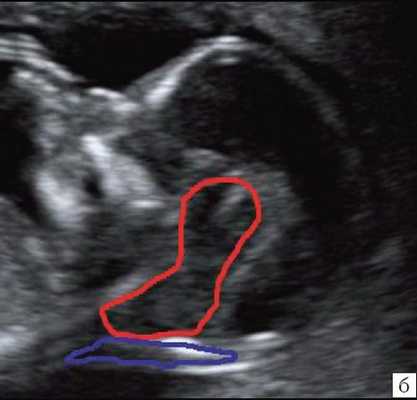

б) Вид "осьминожки":

- красный цвет - диэнцефалон (таламус), со стволом мозга (верхняя ножка) и IV желудочком (нижняя ножка);

- желтый цвет - большая цистерна головного мозга;

- синий цвет - воротниковое пространство.

Новый ультразвуковой маркер в изучении нормальной ультразвуковой анатомии головного мозга плода в срок 11-14 недель беременности

Особенности визуализации изложенных выше структур в данном сроке позволили нам выделить и назвать новый ультразвуковой маркер нормальной ультразвуковой анатомии мозга плода. Структуры головного мозга плода в этой области схожи с осьминогом, у которого есть голова и две приблизительно равновеликие по диаметру ножки, представляющие собой ствол мозга и IV желудочек. Ниже ножек "осьминожки" визуализируется 2 "подушки осьминожки" - это два анэхогенных пространства - большая цистерна и воротниковое пространство (рис. 2, б).

Так как речь идет о сроках первого скрининга, т.е. раннего осмотра, новый ультразвуковой маркер мы назвали "осьминожкой" (рис. 3).

а) Стрелками указана голова "осьминожки" - диэнцефалон (таламус).

б) Красный цвет - диэнцефалон (таламус), со стволом мозга (верхняя ножка) и IV желудочком (нижняя ножка); желтый цвет - большая цистерна головного мозга; синий цвет - воротниковое пространство.